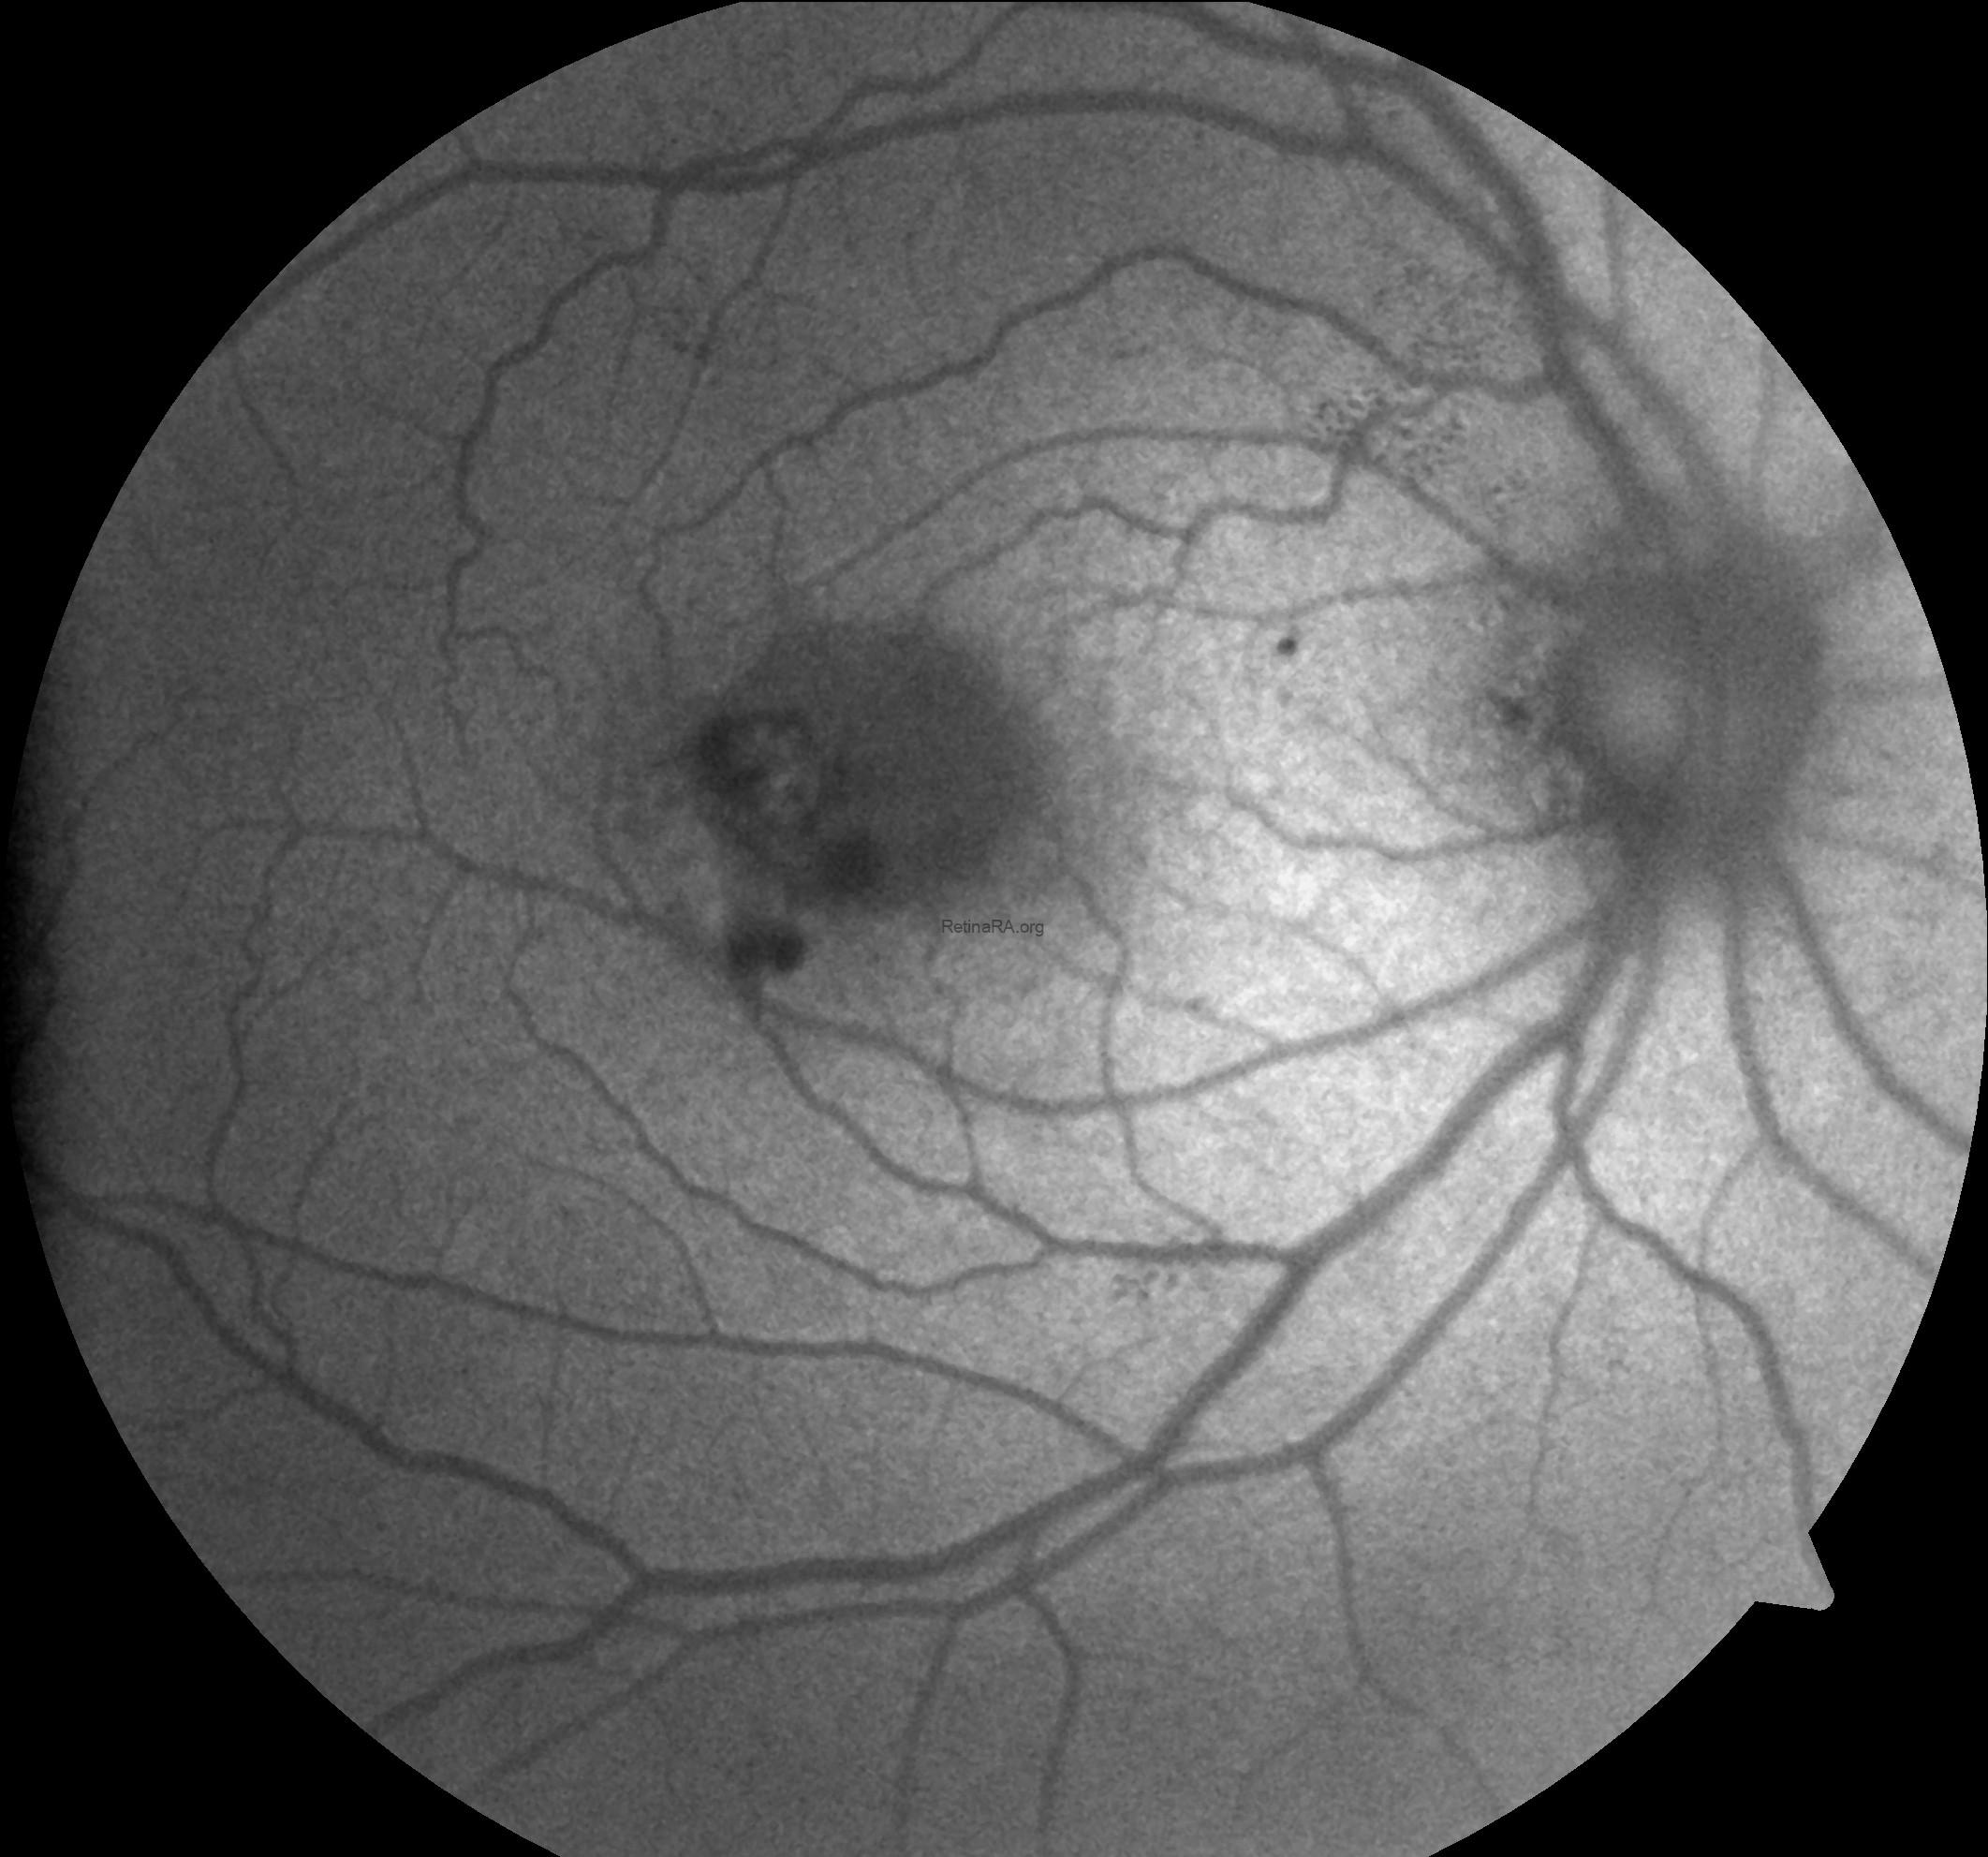

Fundus autofluorescence imaging demonstrated increased parafoveal autofluorescence, most prominently involving the temporal macula, reflecting loss of macular pigment and underlying Müller cell dysfunction. This hyperautofluorescent pattern may become irregular or patchy. Areas corresponding to choroidal neovascularization, subretinal hemorrhage, fibrosis, or retinal pigment epithelium damage appear as focal zones of reduced autofluorescence.

Macular telangiectasia type 2 (MacTel type 2) is a bilateral, neurodegenerative retinal disorder characterized by parafoveal capillary abnormalities and progressive retinal structural changes, which may be complicated by secondary subretinal neovascularization in advanced stages. In the neovascular form, multimodal imaging reveals distinct and complementary findings. Fundus examination may show parafoveal graying, right-angled venules, crystalline deposits, and signs of subretinal neovascular tissue or hemorrhage. Fundus autofluorescence typically demonstrates increased parafoveal autofluorescence, reflecting macular pigment depletion, with superimposed areas of reduced autofluorescence corresponding to neovascular scarring or hemorrhage. Spectral-domain OCT shows inner and outer retinal cavitations, disruption of the ellipsoid zone, retinal thinning, and in neovascular cases, hyperreflective subretinal material associated with subretinal or intraretinal fluid. OCT angiography plays a pivotal role by revealing telangiectatic vascular changes in the superficial and deep capillary plexuses, with neovascular networks often originating from the deep plexus and extending into the outer retinal and avascular slabs. Together, these imaging features support the diagnosis, help differentiate MacTel type 2 from other macular neovascular entities, and guide monitoring and treatment response following anti-VEGF therapy.